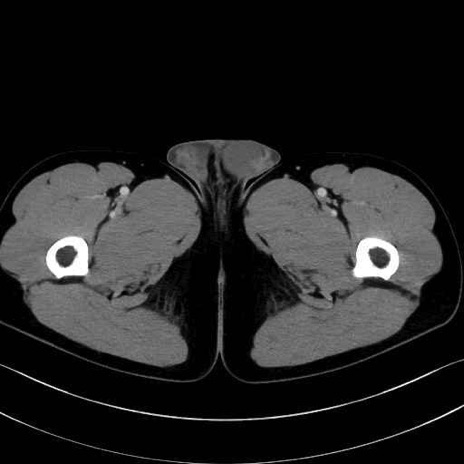

5. 大腿前面(大腿四頭筋群・伸筋群)

縫工筋 (Sartorius)

大腿直筋 (Rectus femoris)

外側広筋 (Vastus lateralis)

中間広筋 (Vastus intermedius)

6. 大腿内側(内転筋群)

恥骨筋 (Pectineus)

長内転筋 (Adductor longus)

短内転筋 (Adductor brevis)

大内転筋・小内転筋 (Adductor magnus / Adductor minimus)